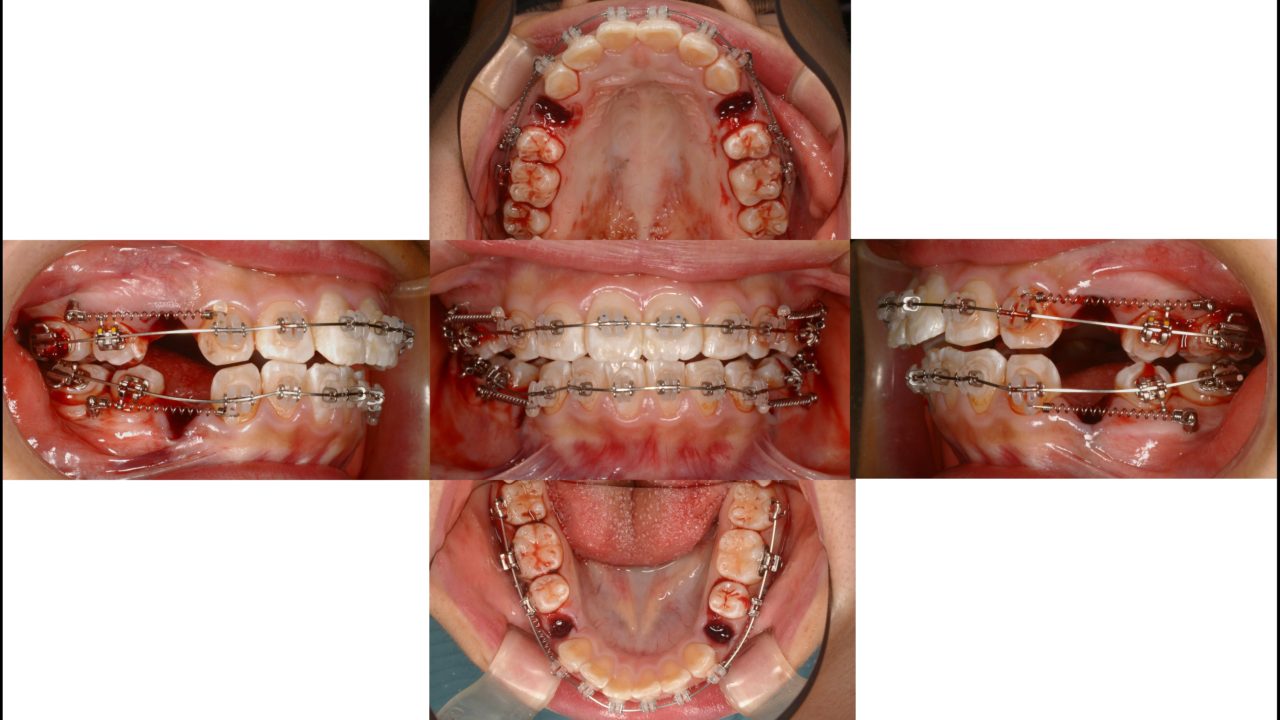

矯正開始 2018.6.11

| 備考 | 小学生のときに他院で第1期矯正をされていました。歯の凸凹は治り歯列はきれいになりましたが、全体的に前に出た仕上がりに不満を持っていました。成長の予測が難しい第1期矯正において、起こりうることです。口元をきれいに引っ込めるために抜歯を伴う矯正治療をすることになりました。第1小臼歯を4本抜歯し、矯正用インプラントにてできるだけ前歯を後方に移動しました。口元が引っ込み、とてもきれいになりました。矯正治療のやり直しはできればしたくないし、さらに結果が求められるので大変ですが、良い結果が出てよかったです。 |